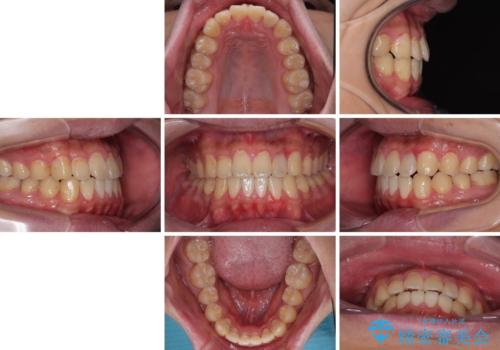

- 前歯のデコボコとクロスバイトを気にして来院された患者様です。

クロスバイトはありましたが、叢生の程度としては酷くなかったため、ワイヤー矯正でもマウスピース矯正でも、好きな方を選択していただきました。

治療開始前は汚れが多く、全体的に歯肉が腫れていましたが、矯正治療を通して腫れも少しずつ改善されました。